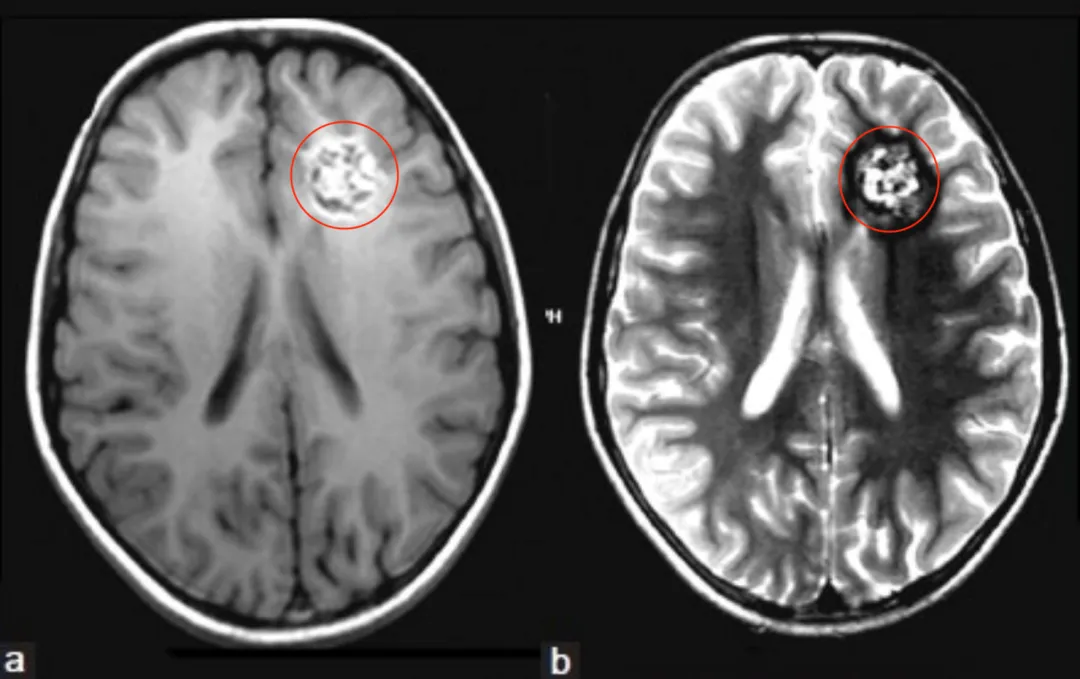

放疗是很多脑瘤患者治疗路上的重要战友,可在经历手术、放疗后,以为终于迎来康复曙光,却不知一种名为放疗诱发海绵状血管瘤的并发症可能正悄然潜伏,可能在治疗后数年突然引发脑出血...